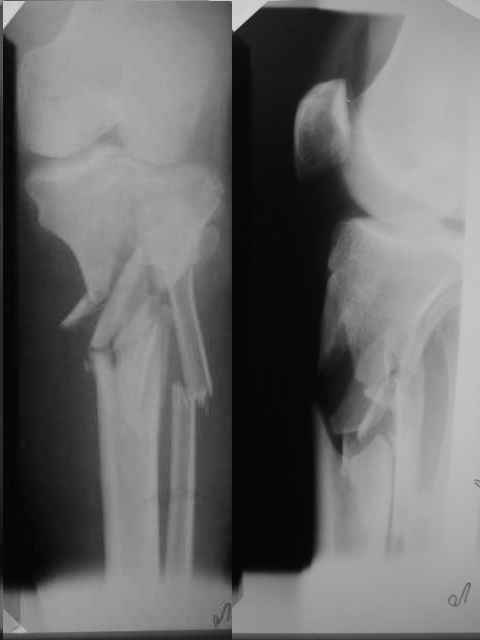

Неудовлетворительная репозиция: вальгус, диастаз по медиальному кортикалу. Наверняка репозиция была открытой недели через две после травмы, а значит травматичной со скелетированием отломков. Наличие в диафизарной части пластины 7 ответстий не означает, что во все надо вводить винты. В метаэпифиз необходимо было ввести минимум 3 блокированных винта на всю толщу спонгиозы.

-Неудовлетворительная репозиция: вальгус, диастаз по медиальному кортикалу.

Вальгуса нет(мы не предоставили осевых снимков)

В диастазе стоит единственный отломок размером 1.2 на 2.5 по медиальной поверхности,остальные отломки всев контакте!

- Наверняка репозиция была открытой недели через две после травмы, а значит травматичной со скелетированием отломков.

Да

-В метаэпифиз необходимо было ввести минимум 3 блокированных винта на всю толщу спонгиозы.

Введено два блокируемых винта длинной 70 мм.и один спонгиозный.

Re: Введение илиосакральных винтов

-Какая (открытая или закрытая) была репозиция?

Репозиция была выполнена открыто(закрыто к сожалению не получилась-большие сроки и множество отломков)

-Чья это пластина?

LCP"SYNTHES"-прокимальная латеральная для б/берцовой кости